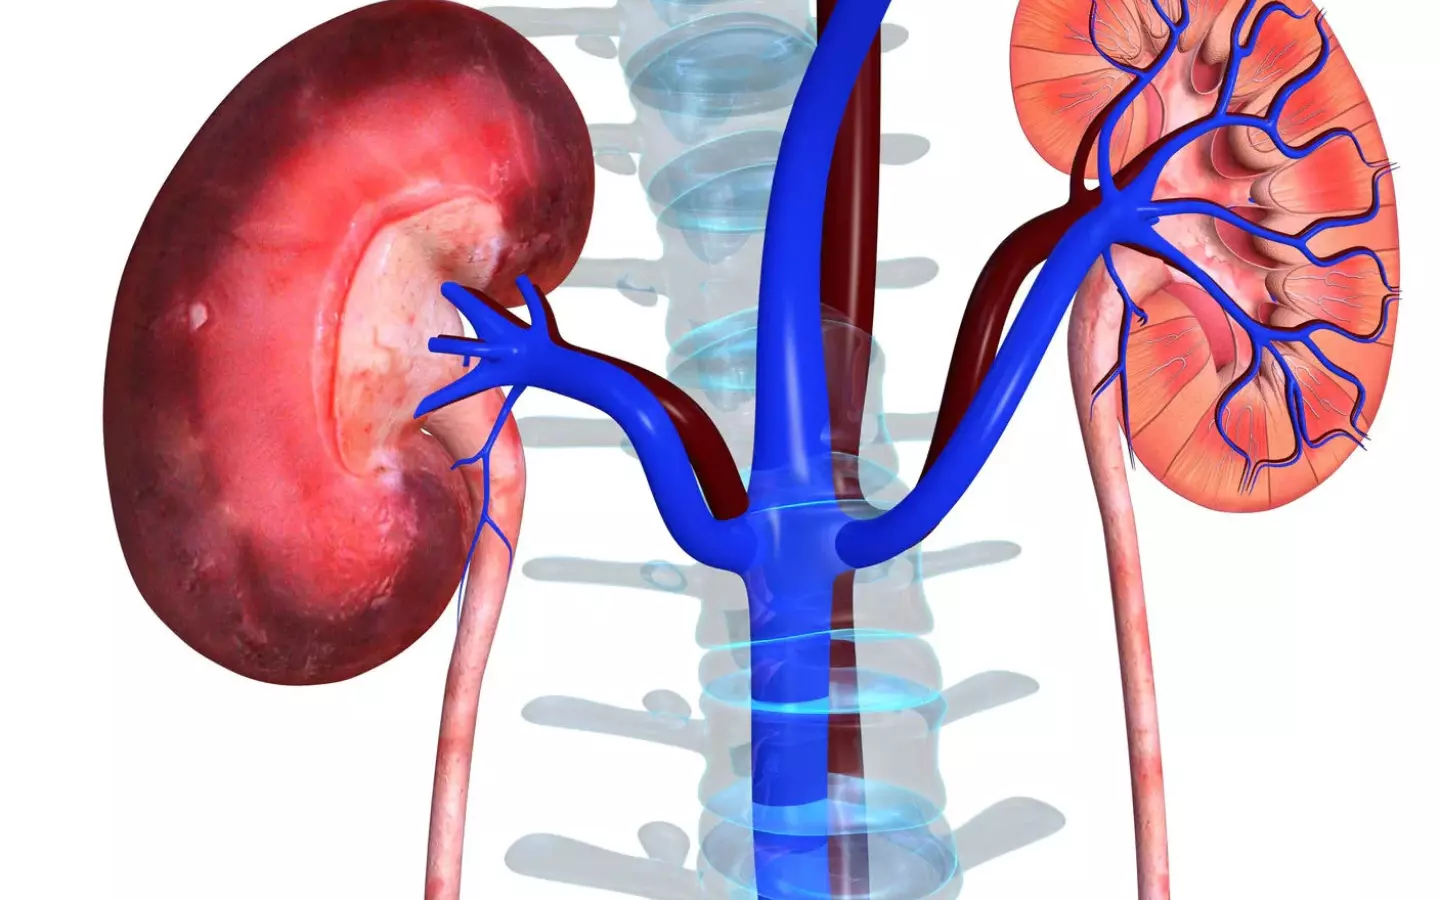

Read moreLifestyle, Diet and Kidney Disease

Kidney disease, often referred to as chronic kidney disease or CKD, is the loss of kidney function over a period of time ranging from several months to several years. KCD is very common and can affect anyone regardless of health or age. Without dialysis treatment or a transplant the...